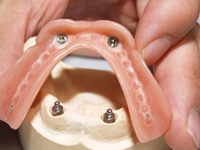

Bezzubá čelist

Pevné můstky – lepené nebo šroubované

Třmeny

Kulové attachmenty

Sub-Tec Locator®

Metoda All-on-four

Bezzubá čelist je hlavní indikací pro ošetření pomocí implantátů. Zejména celkové zubní náhrady v dolní čelisti mají velice nízkou stabilitu a držení díky velkému úbytku kosti.

S pomocí zubních implantátů můžeme díky různým kotevním systémům (třmeny, kulové hlavy, Locatory) zajistit stabilitu a držení protézy nebo při použití většího počtu implantátů zhotovit pevné náhrady – můstky nalepené nebo našroubované na pevno na implantáty.

S těmito typy náhrad můžeme dosáhnout perfektní funkci, výbornou estetiku, fonetiku a současně zajistit u pacienta možnost dobré hygienickou péče a čištění, která je pro životnost implantátů velice důležitá.